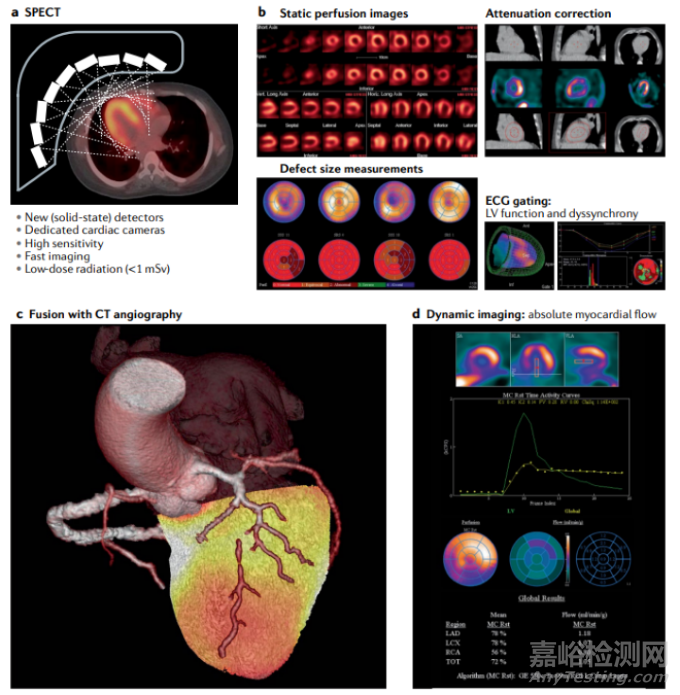

近年來,SPECT心臟顯像設(shè)備和軟件技術(shù)均有較大的進(jìn)展。以Spectrum Dynamics(光脈醫(yī)療)的DSPECT和GE HealthCare的NM530c為代表的兩款心臟專用SPECT設(shè)備,采用模塊化半導(dǎo)體高性能探測器及聚焦準(zhǔn)直器技術(shù),實(shí)現(xiàn)了針對心臟的高分辨率和高靈敏度顯像,不僅提升了心肌灌注顯像的圖像質(zhì)量且降低顯像時(shí)間,更具備了動態(tài)顯像能力,可以實(shí)現(xiàn)心肌血流定量顯像和診斷功能,已經(jīng)在臨床較為廣泛的應(yīng)用,如下圖21所示。目前,心臟專用SPECT的主要局限在于缺乏CT模塊(GE公司帶CT模塊的NM570c心臟專用SPECT/CT一體機(jī)已經(jīng)不再供貨),因此導(dǎo)致衰減校正缺失,定量準(zhǔn)確性不高,同時(shí)無法利用同機(jī)精準(zhǔn)融合的CT信息輔助診斷。針對這一局限,國內(nèi)外相關(guān)公司紛紛推出或積極研制現(xiàn)在心肌顯像方面有特色的SPECT/CT一體機(jī)產(chǎn)品,如下圖22所示。

圖21:a、新型基于半導(dǎo)體探測器聚焦心臟成像的心臟專用SPECT原理示意;b、a中所示設(shè)備的代表性心肌灌注圖像;c、SPECT心肌灌注圖像與CT冠脈造影圖像融合與三維顯示,展示冠脈狹窄與心肌缺血的對應(yīng)關(guān)系;D、基于a設(shè)備的心肌血流絕對定量動態(tài)顯像。圖片引自參考文獻(xiàn)[6]